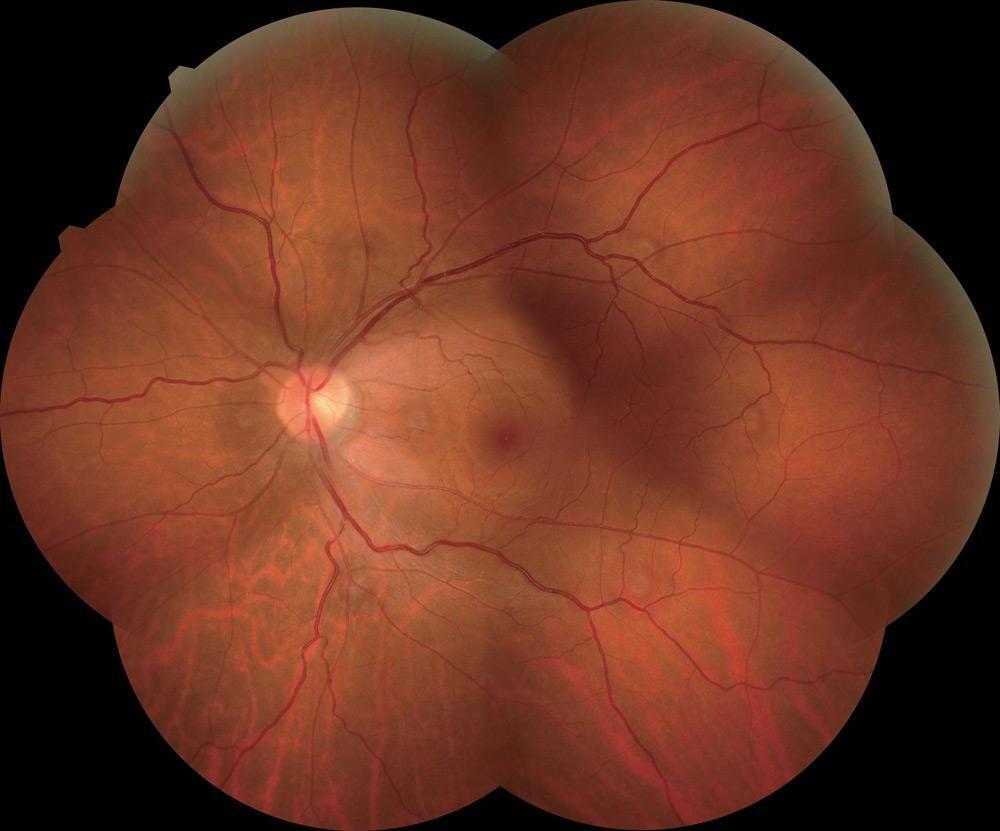

Rétinopathie Diabétique

Examen du fond d'œil pour les patients diabétiques. Collaboration Médecin généraliste – Orthoptiste – Ophtalmologue.